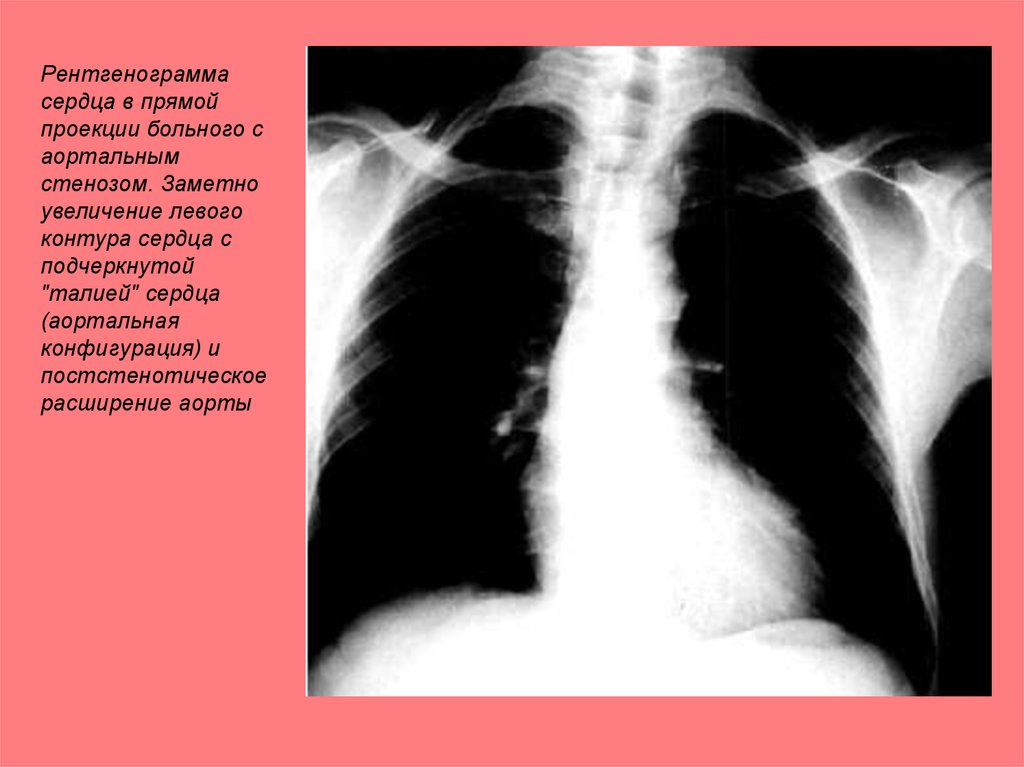

Рентгенограмма

сердца в прямой

проекции больного с

аортальным

стенозом. Заметно

увеличение левого

контура сердца с

подчеркнутой

"талией" сердца

(аортальная

конфигурация) и

постстенотическое

расширение аорты